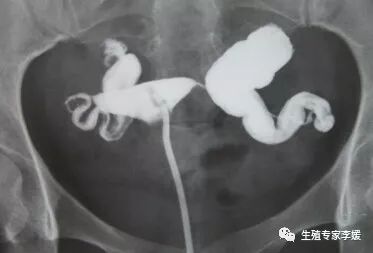

卵管积水是一种特殊类型的输卵管梗阻,不仅影响输卵管运输功能,输卵管中积聚的炎性积液可能逆流入宫腔造成子宫内膜炎症,影响子宫内膜容受性,除此之外还会毒杀胚胎、机械性冲刷胚胎,对胚胎造成不良影响。并且输卵管积水还会压迫卵巢供应血管,影响卵巢功能。

输卵管积水常见的处理方法有:输卵管切除、输卵管结扎、输卵管造口术、超声引导下输卵管积水抽血术、输卵管栓塞术等。不少女性对处理输卵管积液所行的手术持有顾虑,比如本文提到输卵管结扎术。需要说明的是:任何操作、手术对身体可能造成危害是不能否认的,没有绝对零伤害的操作或者手术。但是采取该种手术、操作的获益大于疾病所致的弊端,我们就认为这种手术或操作是值得的,有必要实行的。输卵管积水对女性生育的负面影响是毋庸置疑的,并且输卵管积液处理后可以改善IVF-ET结局也是公认的。所以对于不孕不育女性,如果想要获得良好的临床或妊娠结局,如果存在输卵管积水,必须积极处理。

输卵管结扎术是目前常采取的方法之一,该手术阻断了输卵管中炎性积液进入宫腔,但是输卵管中的积液并未去除,有可能造成盆腔炎症,并且输卵管积液还可能继续对卵巢供应的血管产生压迫,影响卵巢功能。当然其他几种方法也各自存在利弊,最终采取哪种方法,需临床医生根据病情而定。